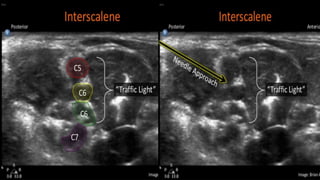

ULTRASOUND GUIDED TECHNIQUE

• TRANSDUCER(>12MHZ) IS PLACED IN THE MIDLINE AT THE LEVEL OF CRICOID

CARTILAGE

• THE FIRST TWO STRUCTURES ARE IDENTIFIED ARE CAROTID ARTERY & INTERNAL

JUGULAR VEIN

• THE PROBE IS THEN MOVED IN A LATEROPOSTERIOR DIRECTION APPROX. 1-2CM

• THE BP CAN BE SEEN BETWEEN ANTERIOR & MIDDLE SCALENE MUSCLES AS

DISTINCT HYPOECHOIC CIRCLES & HYPERECHOIC RINGS

• USING “IN PLANE APPROACH” THE NEEDLE IS INSERTED THROUGH EITHER

MIDDLE SCALENE MUSCLES OR ANTERIOR SCALENE MUSCLES

• NEEDLE IS ADVANCED UNTIL A DISTINCT POPPING SENSATION IS BOTH FELT &

VISUALIZED TEST INJECTION SHOULD BE GIVEN VISUALIZING FILLING OF BP